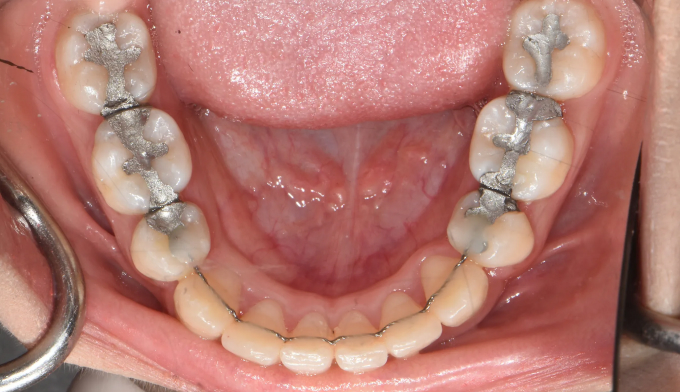

매복치, 덧니

매복치의 경우 무조건 교정을 통해 구강내로 견인해야 하는건 아닙니다.

교정을 했을때의 득과 실을 살펴보는것이 중요합니다. 너무 깊숙히 묻혀있는 치아는 그냥 놔두는것이 나을때도 있습니다.

매복치에 접근하는것이 무리라고 판단되어 유치만 발치하고 진행하기로 하였습니다.

아래치아도 갯수를 맞춰주기위해 하나씩 발치하였습니다.